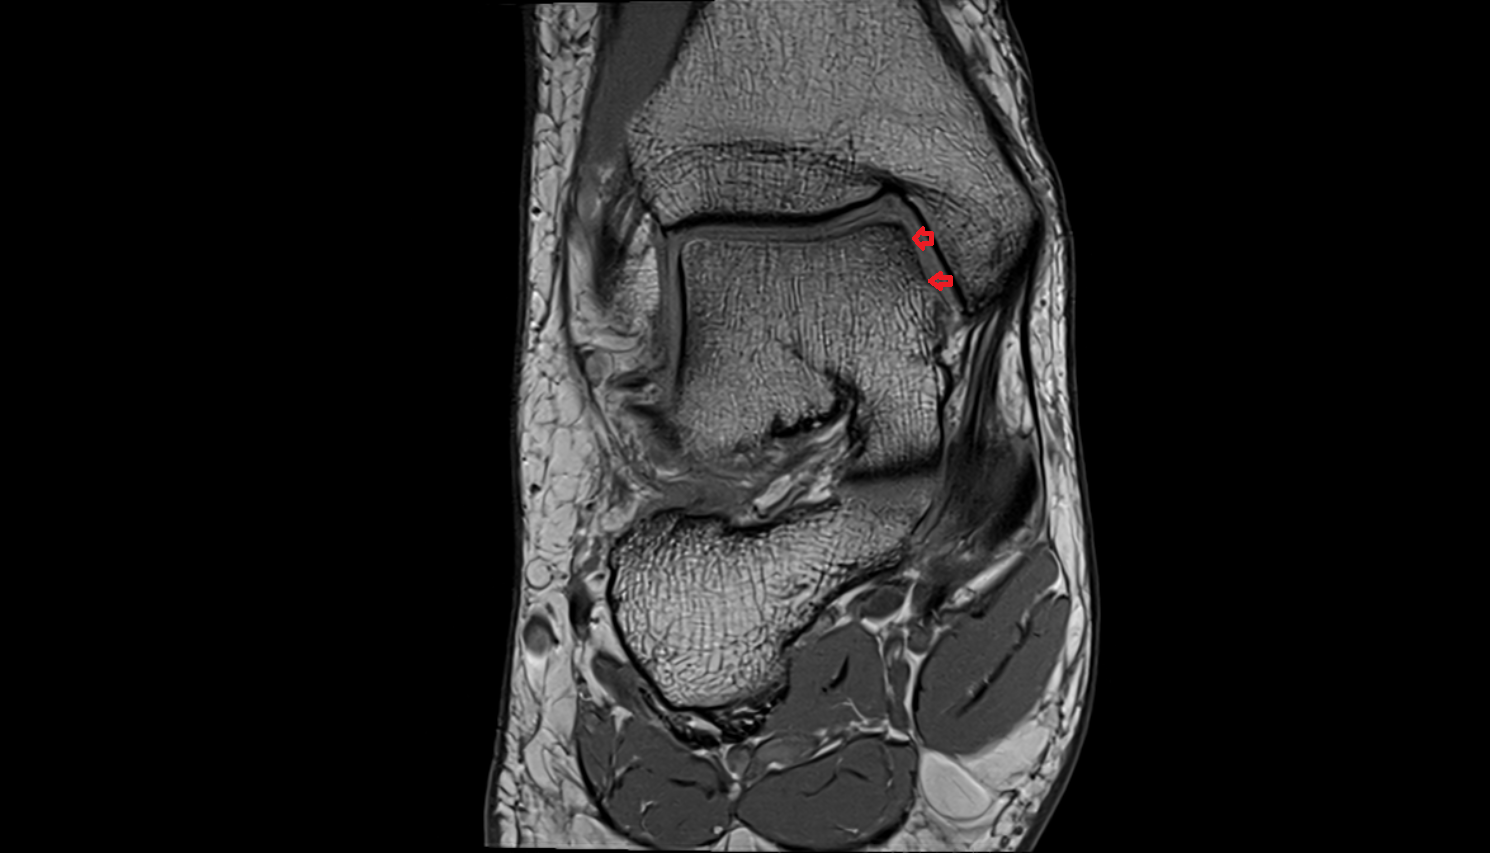

- Ankle joint

- Talus

- Calcaneus

- Anterior talofibular ligament

- Posterior talofibular ligament

- Deltoid ligament complex